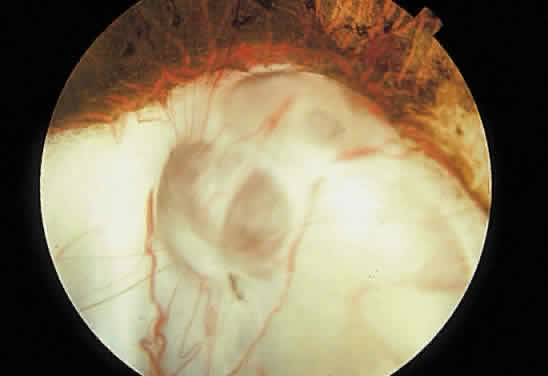

Fig. 13. Retinochoroidal coloboma involving the optic disc and inferonasal fundus. The borders of the abnormality are nonpigmented, and the defect appears to be filled with fibroglial tissue.

Embryologically, retinochoroidal colobomas arise from failure of the embryonic fissure to close. Consequently, the inner and outer layers of the optic cup are abnormal in this region. The inner layer (sensory retina) usually is present as a membrane of undifferentiated retina that may have blood vessels going through it (see Figs. 12 and 13). The outer layer (RPE) is absent, and since the choroid is dependent on the RPE for its development, it also is lacking.